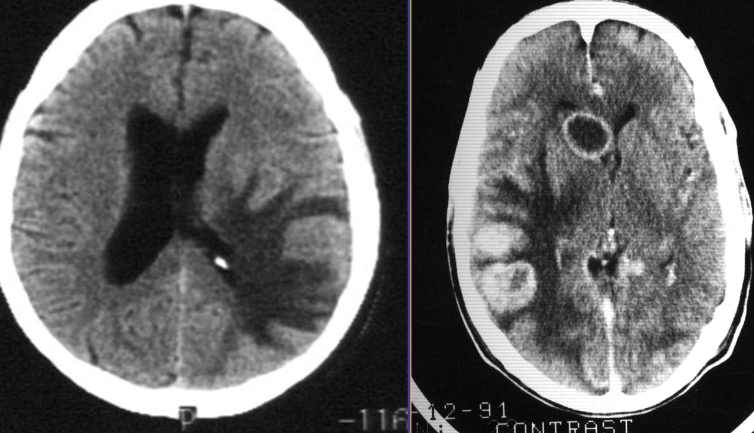

A. Give the name of the pattern of contrast enhancement of the lesion

- Contrast CT*

B. Give ONE cause for the pattern of contrast enhancement shown Enhanced lesion: Lesion which shows contrast uptake

A. Give the name of the pattern of contrast enhancement of the lesion in the given image

. (a) Post contrast CT scan showing a right frontal low density ring-enhancing lesion with surrounding vasogenic oedema

B. Give ONE cause for the pattern of contrast enhancement shown in the given image Cerebral abscess